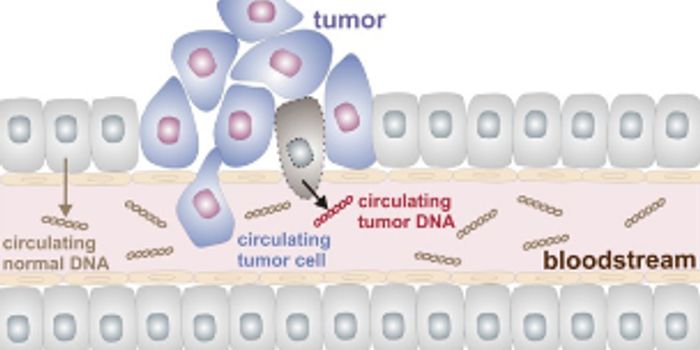

FEB 24, 2016Clinical & Molecular DXCancer cells are exquisitely cunning – they mutate and adapt to escape the body’s own defense mechanisms, an ...

JUN 27, 2022CancerCancer develops when the DNA in our cells becomes altered, resulting in a gene mutation. DNA alterations can occur ...

MAY 05, 2022CancerHumans develop cancer at a remarkably high rate in comparison to other animals. Many elements are attributed to th ...